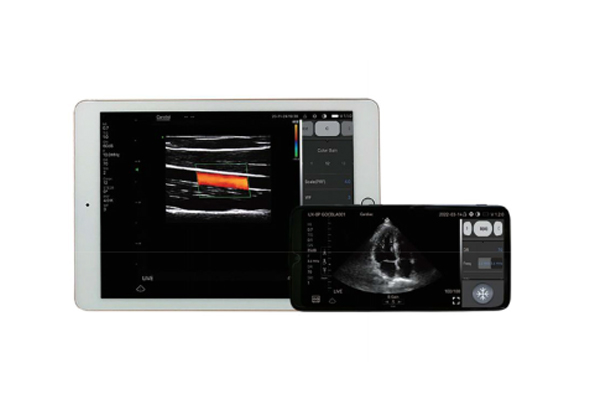

Ultrasound Scanner RK-4CPL

- remote interconnection, intelligent sharing

- waterproof disinfection, safe and reliable

- easy disinfection and remote diagnosis

Wireless ultrasound probe" is a miniultrasound scanner that without screen.We made the main unit condensed into a small circuit board builded-in theprobe, and showing image in smartphone/tablet through Wifi transferring.-Image transferring through internalwifi from probe, no need external Wifi signal.